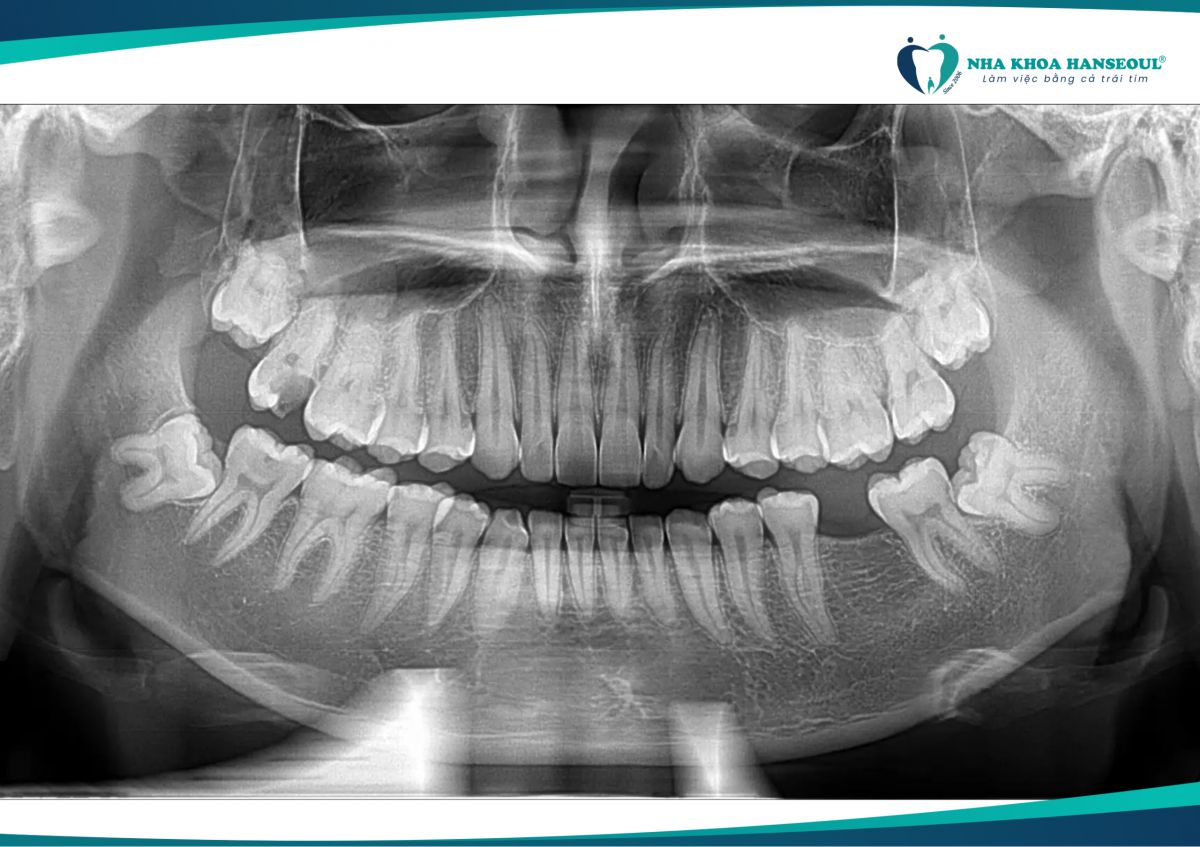

Đầu tiên, anh Trọng được bác sĩ thăm khám kỹ lưỡng và chụp phim CT 3D để xác định chính xác vị trí răng khôn. Sau đó, bác sĩ tiến hành gây tê một cách nhẹ nhàng, hoàn toàn không cảm thấy đau đớn gì. Với công nghệ Piezotome hiện đại, quá trình nhổ răng diễn ra nhanh chóng.